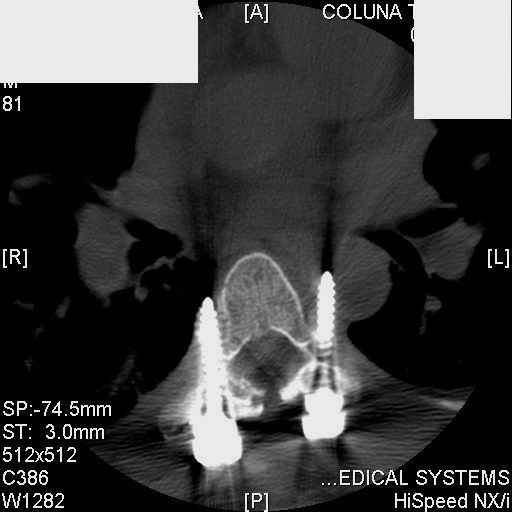

Interesting case. Findings on CT: all four pedicle screws have been placed improperly inthat they miss the vertebral bodies. In addition, the screws on the left side are impingingon the decending thoracic aorta. What I do NOT know is the nature of the original injury, orwhether or not that injury has resolved. I would recommend removal of the hardware. I don'tthink it's a good idea to leave those screws where they are. If the original fracture ishealed, nothing else needs to be done.

dear Mark, all the details are not yet available but the patient is coming to see us foradvice. We probably will see him in the early new year. i thought that the 4th picture showedthe screw to enter the aorta? He is a victim of a motor vehicle crash and thoracic vertebralfracture which appears healed. He was posteriorly decompressed and this device inserted. asyou say there isno evidenece that any of the fixation enters the bodies via the pediclesistead they have passed thru and their end are no where near where they ought to be. If I amcorrect (I would prefer not to be) the aortic intima has been breached by the screw. When thetime comes to take the screw out I thought we should have control of the aorta.What do you think?

Tom: I strongly doubt that the aorta is involved. When these screws are put in, they firstput in a probe, then a tap, then the screw. If the aorta was punctured, they would have knownat the time. You might call the original surgeon (if in fact he is a real doctor) and get hisfeedback. The additional morbidity of a prophylactic thoracotomy would be a higher pricethan I would be willing to subject my patient to. Besides, it would be exceptionallydifficult to control the aorta at this point, especially if you tried to specifically getenough control to be able to put sutures in the back wall. Of course, difficulty of doingsomething isn't necessary a reason not to do it if you think it is necessary. I just think itis highly unlikely that the aorta is injured. I showed the case to both a thoracic surgeon anda neurosurgeon. The thoracic surgeon suggested getting an arteriogram to see if the aorta isinvolved. The neurosurgeon agreed that the hardware should be removed.

Mark Thank you. He is scheduled for a angio prior to transfer here. I keep going back to lookat that fourth image and although it is tough to believe the wall of the aorta seems toencompass the distal 1/2 of the screw. I have come to anticipate mal postion of screws thathave been inserted in hospitals that perhaps may not have the highest quality of equipment,including the human and radiological components. That having been said this case seems tosurpass the usual... one screw out of place or screwed into a disc etc. BTW I am notsuggesting that the screw was placed directly into the aorta but that moviment, pulse actionetc may have caused it to transgress the normal anatomical bounds without evident hemorrhage.